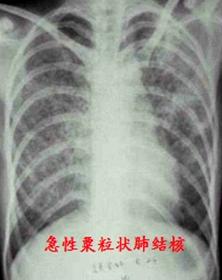

3、 肺结核患者

通常肺结核患者X光胸片可有较为典型的影像特点,配合午后盗汗、低热、消瘦等临床表现可以判断为结核病。但近年来我国结核病检出率有所上升,且影像学、临床症状都不典型,难以和肺炎、肿瘤等肺部疾病鉴别,因此诊断时还需要配合细菌学、免疫学等检查共同判断。

急性肺结核如粟粒状肺结核,通常可见全肺均匀弥漫的粒状阴影。而慢性结核及结核病后期,病灶会逐渐缩小,肺部会形成结核球或空洞的钙化灶点,包裹住结核杆菌,使病情得到控制。